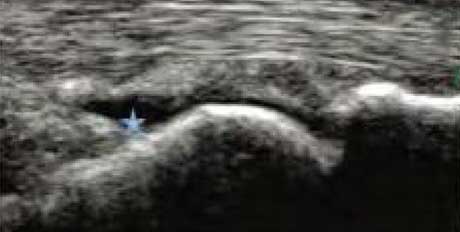

3、准确判断关节积液增加,精准判定RA严重程度

类风湿关节滑膜炎症会导致滑液渗出不断增多,形成关节腔积液。肌骨超声 少可发现1ml的积液,能对关节腔积液量及位置准确定位,通过检测判定关节腔内液性边界清楚的无回声区、细点状回声或细微的低回声条纹,判断其宽度和深度衡量积液量的多少,进而评估RA的严重程度。

Ⅰ级微量积液

滑膜囊内见前后径3.55mm液性暗区,呈椭圆形

Ⅱ级较多量积液

暗区内有团状高回声,可见深度达6.46mm液性暗区

Ⅲ级大量积液

关节囊扩张,可见大范围液性暗区,髌上囊积液深度达11.2mm